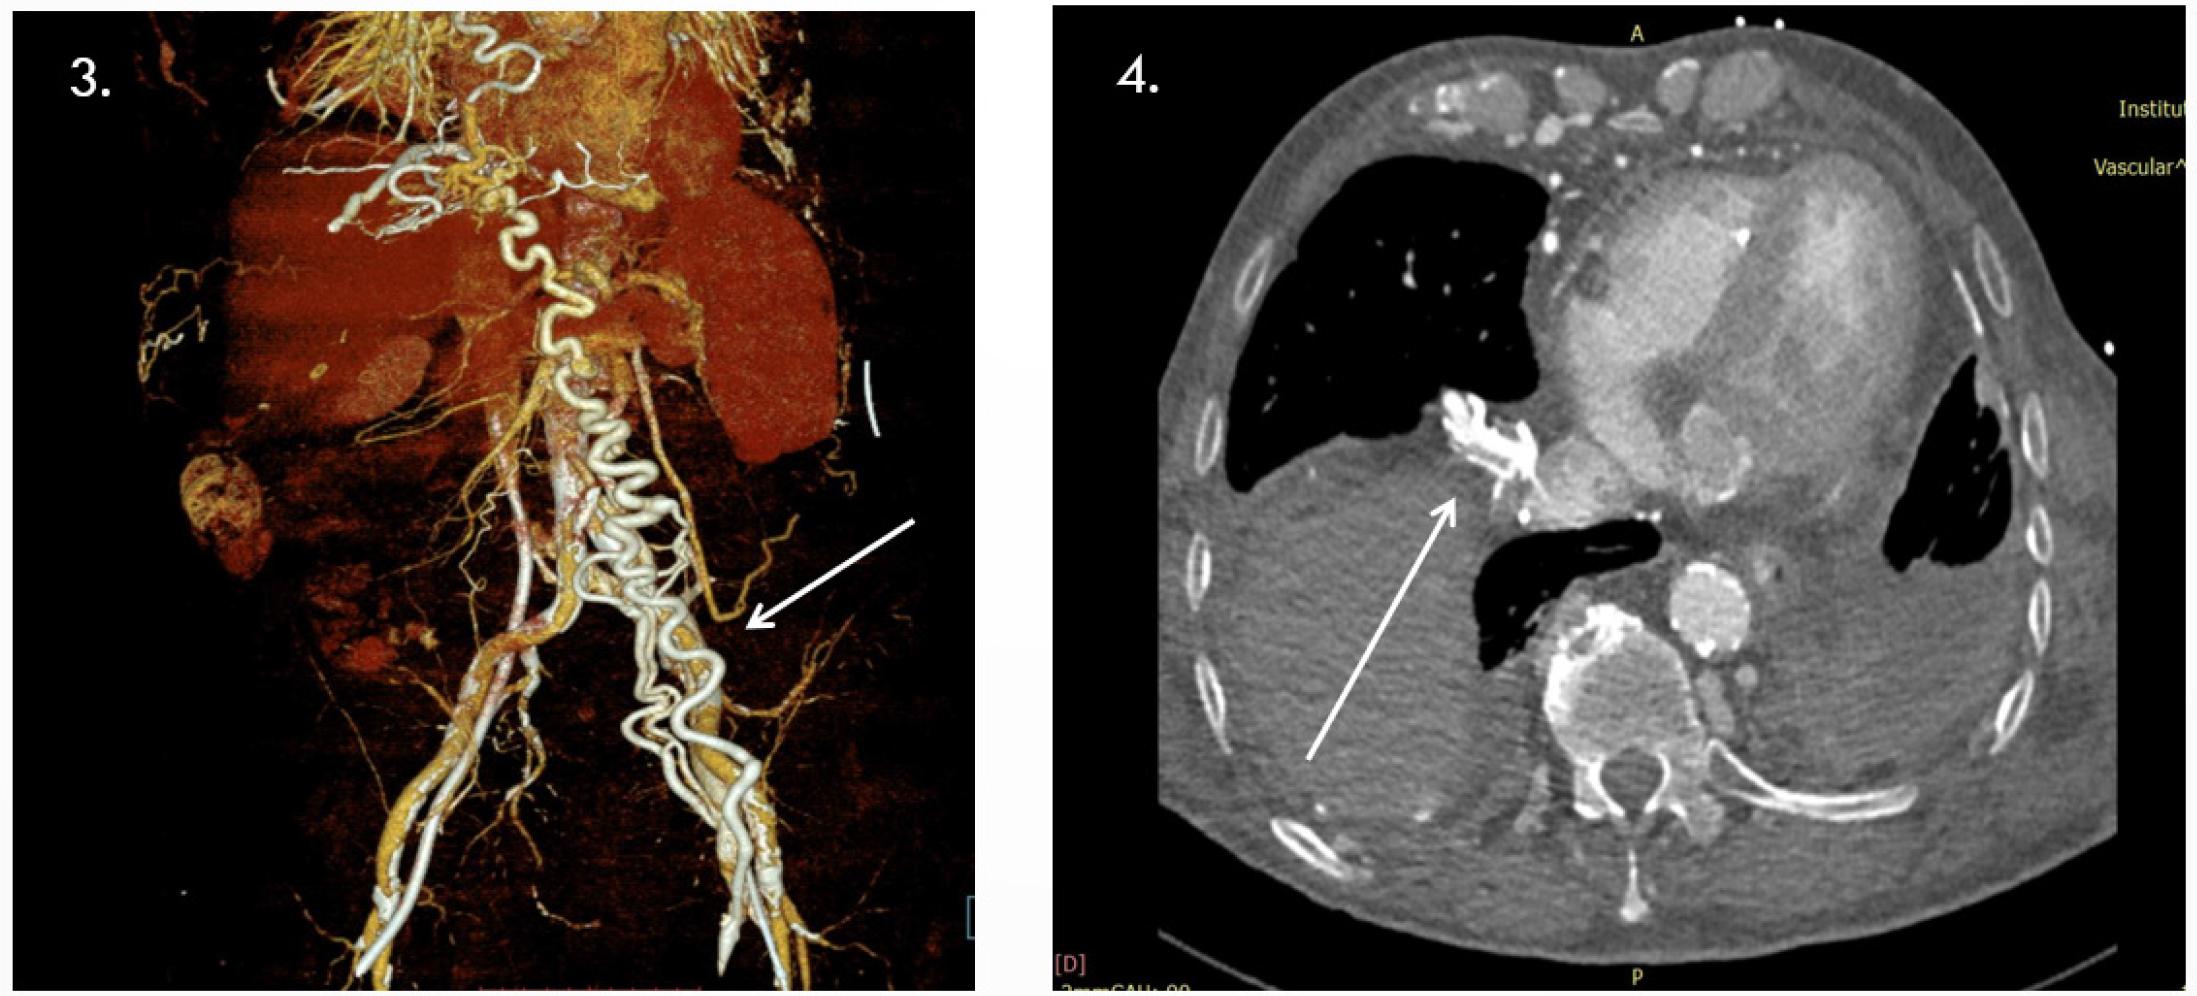

3- Important collateral circulation thoraco-abdominal; 4- Important collateral circulation thoraco-abdominal.

Contrast-enhanced CT via the right antecubital vein revealed severe proximal IVC stenosis (~9 mm length, residual lumen 1–2 mm, 2.5 cm above iliac confluence) with partially calcified thrombus, extensive collateral venous circulation, ruptured calcified catheter fragments, and a right iliac venous stent. The left common iliac vein was ligated with collateral flow; the left renal vein was dilated. The aorta showed diffuse calcification and stenosis, with focal ectasia and thrombus at the IMA origin raising suspicion of a small aorto-duodenal fistula. Significant stenoses were also noted at the SMA and celiac origins, with heavily calcified iliac arteries (Summary Figures 5).